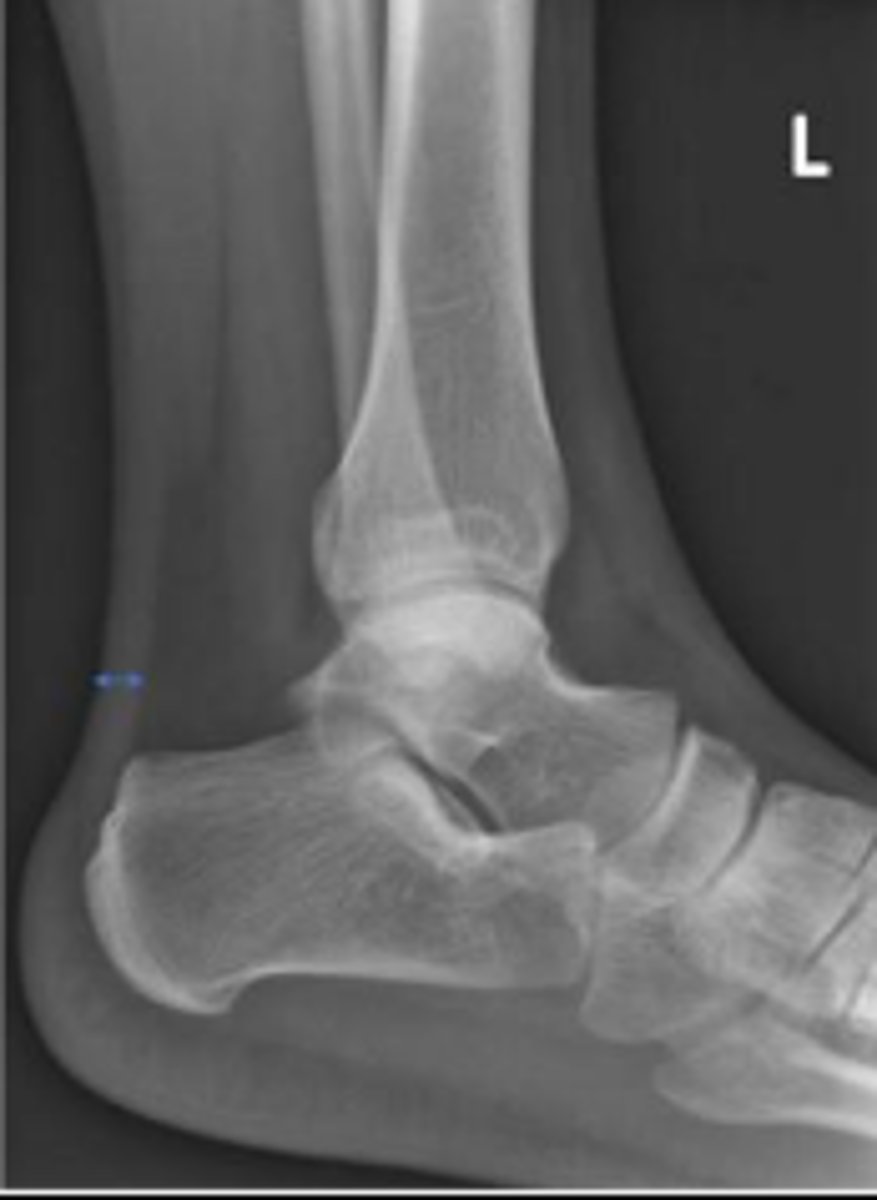

Left AP ankle

What is the name of the radiographic view?

Left distal tibia

What bone are the arrows pointing to?

Left distal fibula

Achille's tendon of the left ankle

What are the arrows pointing to?

Talus of the left ankle

What space are the arrows pointing to?

Cuboid of the left ankle

What is the arrow pointing to?

Kager's fat pad of the left ankle

What is outlined?

Left fibula

What bone are the arrows pointing t